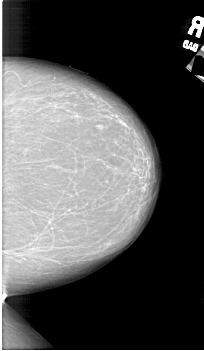

A_1802_1.LEFT_MLO

LEFT_MLO LINES 6871 PIXELS_PER_LINE 4216 BITS_PER_PIXEL 12 RESOLUTION 43.5 OVERLAY